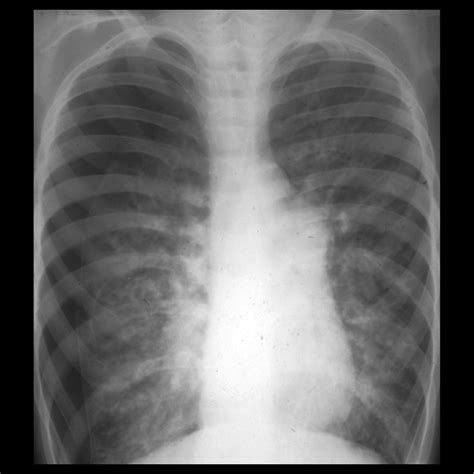

• Chest X-ray: This is the primary diagnostic tool for pneumothorax. A chest X-ray can show the presence of air in the pleural space and the extent of the lung collapse.